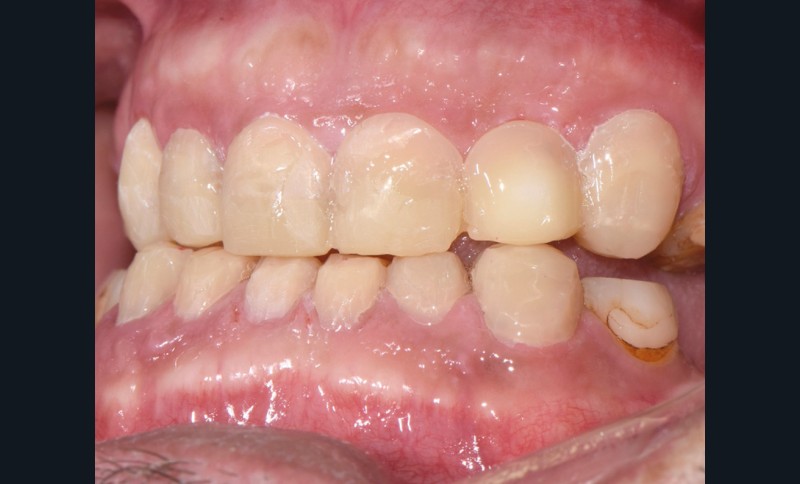

Au vu du contexte para-fonctionnel et de l’étendue de la perte tissulaire, des coiffes périphériques minimalement invasives ont été choisies afin de restaurer l’esthétique et la fonction. Actuellement, aucun consensus n’est fait sur le choix du matériau d’infrastructure à privilégier. Les matériaux hybrides usinables présentent des propriétés mécaniques, physiques et biologiques intéressantes en contexte d’usure sévère (e.g., module d’élasticité, résistance à la propagation de fêlures, facilité de réintervention). Une réhabilitation globale avec remontée de dimension verticale d’occlusion (DVO) par l’intermédiaire de coiffes composites renforcés en nano-céramiques est décrite.